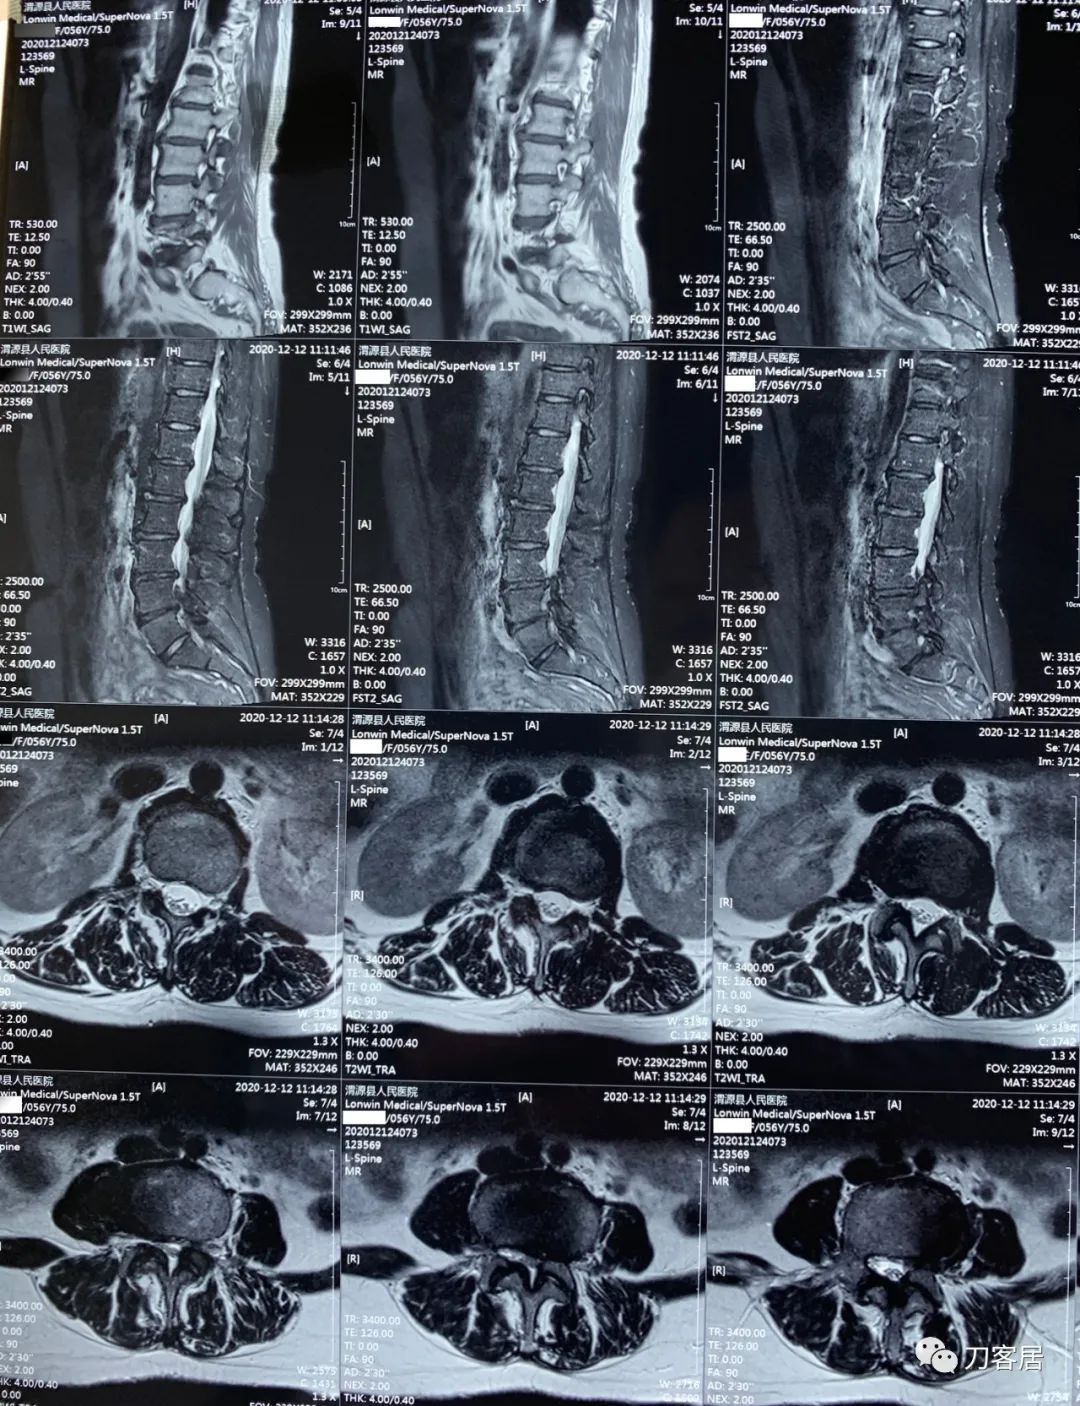

2021年12月12日去渭源县医院做颈椎腰椎MRI,提示1.腰椎侧弯畸形并骨质增生,2. L5S1椎体终板炎(I型), 3. L1-S1椎间盘变性并腰2-4,腰5骶1椎间盘膨出,腰4-5椎间盘突出并相应平面继发性椎管狭窄。2020年12月中旬于渭源县医院行骶管注射2次6针后睡眠改善,

2021年5月17日,西京医院骨科门诊找我就诊,自带影像学检查资料提示腰椎侧弯,腰3-4,腰4-5椎间盘突出,黄韧带肥厚,椎管狭窄。

从这个患者的影像资料分析,颈椎间盘突出问题不大,没有明确的上位神经元损伤表现,所以,不考虑颈椎和胸椎问题。腰椎侧弯畸形,但不严重。因为存在腰椎侧弯,使得腰椎MRI在扫描切面的时候,显示的椎间盘突出或椎管狭窄会有一定的误差,所以,又加做了经椎间盘的CT平扫,影像表现并不严重,综上,腰椎间盘突出,腰椎管狭窄,腰椎侧弯,不考虑手术治疗。同时,患者的主要痛苦是心理疾病,而不是器质性疾病,所以,以心身疾病治疗为主。虽然患者骨密度检查结果提示正常,但X线片显示骨质疏松,且其症状也与骨质疏松的症状有符合之处,比如静息痛,不能入睡,动作及姿势变换时痛加重等,所以,给予实验性抗骨质疏松治疗,以观疗效。